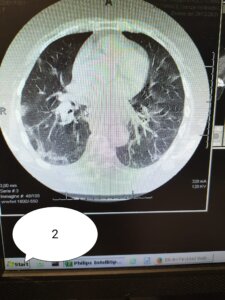

Galmozzi ha poi pubblicato 3 immagini di TC:

2) soggetto di 70 anni NON VACCINATO, senza malattia in anamnesi

“Se in 1) e 2) il carico di malattia polmonare è elevato in 1 (circa 60%) e discreto in 2) (circa 35%). Nel soggetto 3) (fragile e con malattie importanti in anamnesi), la malattia non c’è. I primi due ricoverati e con ossigeno, il terzo a casa sua”.